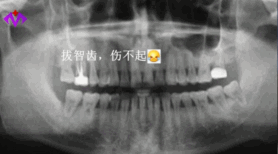

明明知道智齒就是口腔里的“定時炸彈”,極容易導致智齒冠周炎、損害鄰牙等問題,卻因為怕疼、怕麻煩、想省錢,非得等到問題爆發(fā),才肯踏進牙科的大門。

智齒長的位置不同,拔除的收費也不一樣。